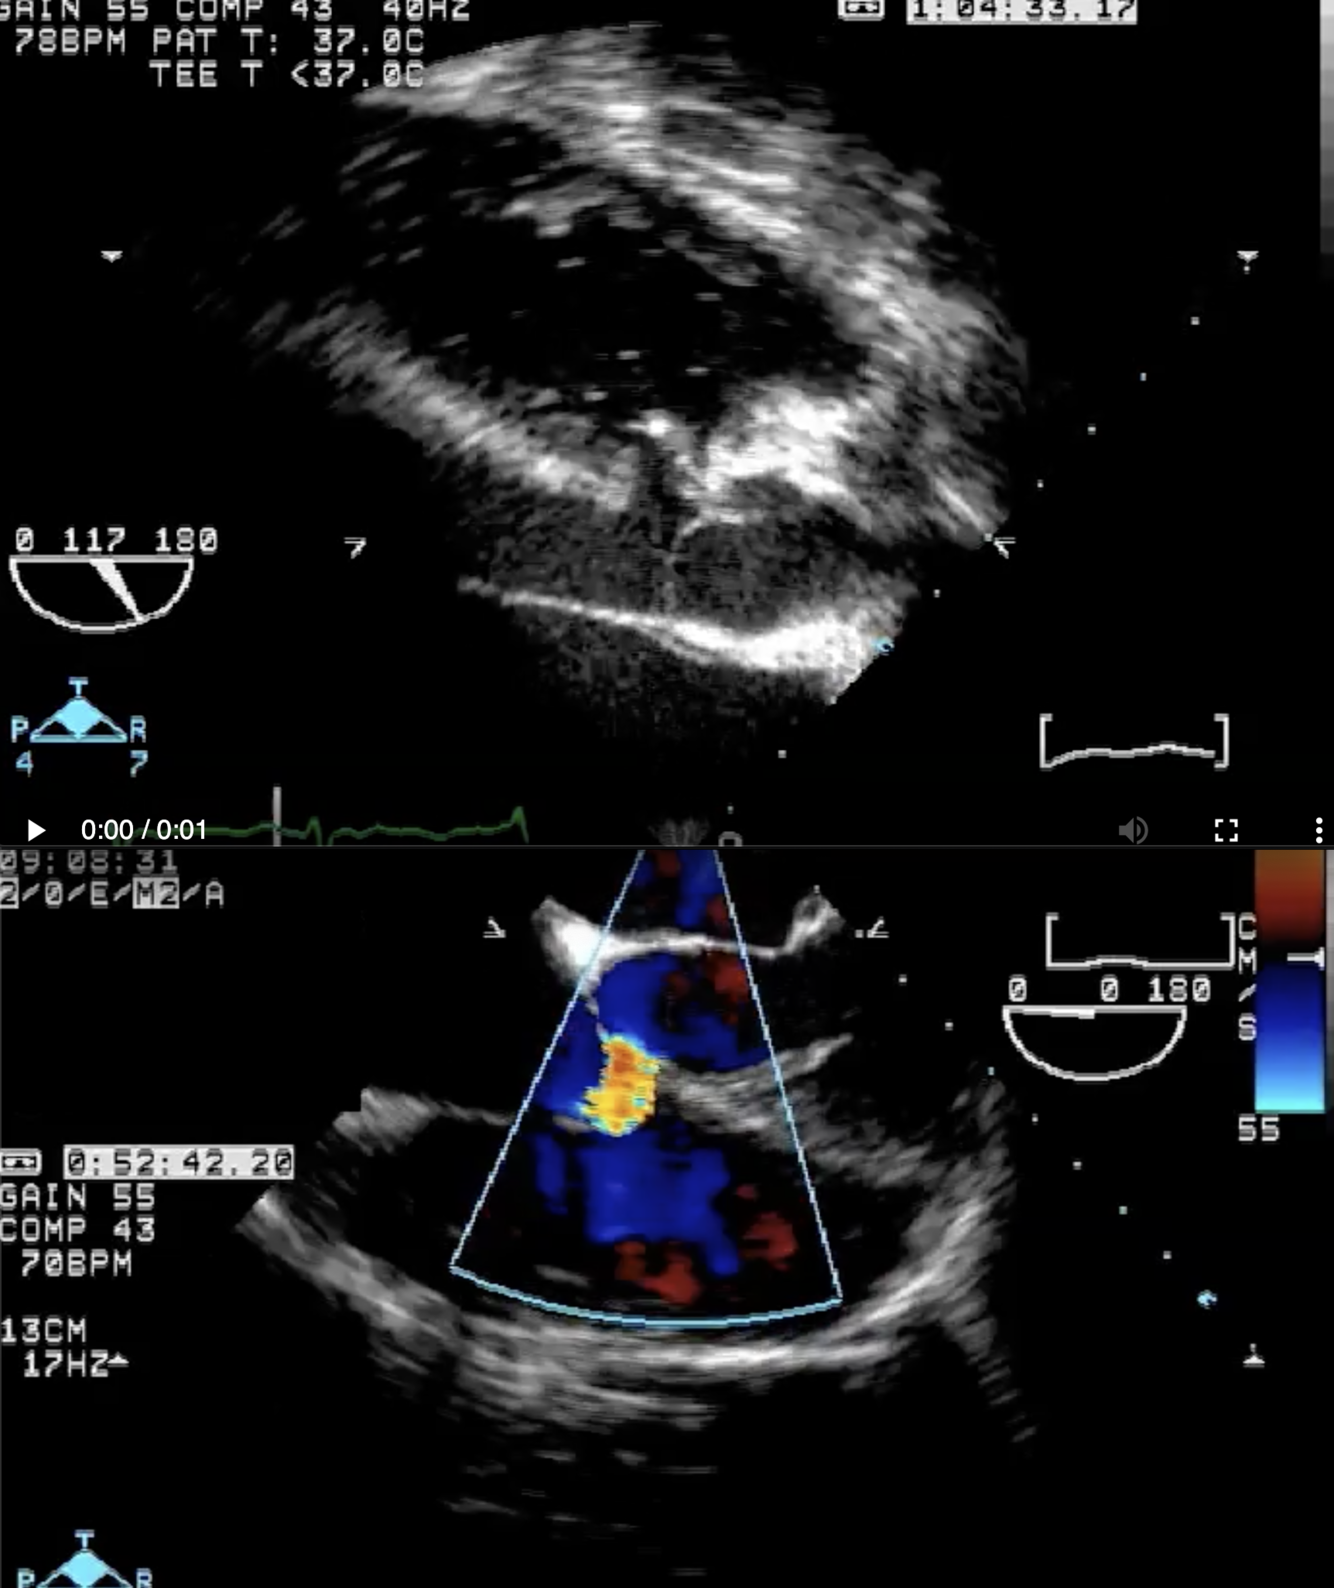

Describe the findings:

*****Dx: HCM with prior apical MI –> LV apical aneurysm

******mid-cavity obliteration during systole –> LVOTO

*******mechanism of MR in this setting –> systolic anterior motion of anterior MV